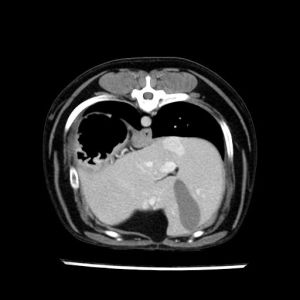

La lesione focale epatica , la ceus,la Tac e il chirurgo .